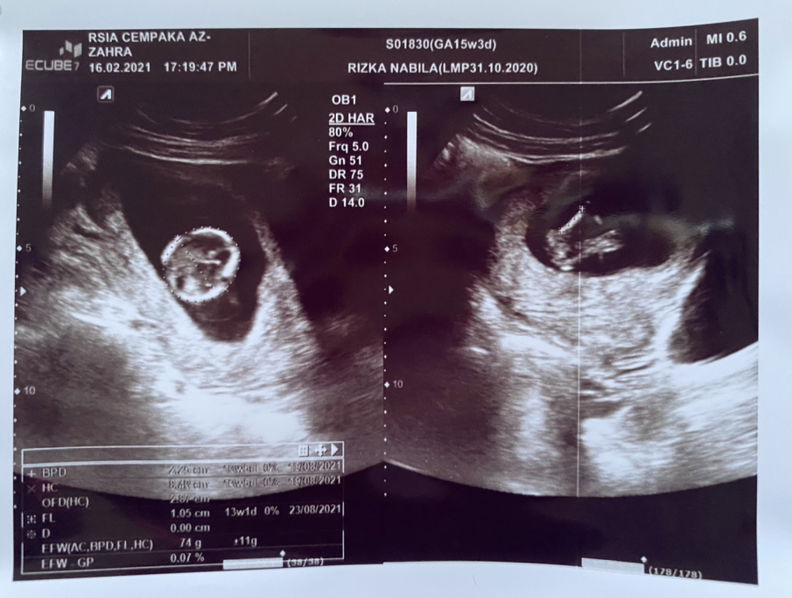

saya waktu itu makan hehe malah pernah makan duren sampe 3 buah, karna blm tau kalo hamil. skrg jalan 15 week sehat debaynya , malah udh keliatan jk nya ๐ minta doa nya bunda bunda

sedang mengandung